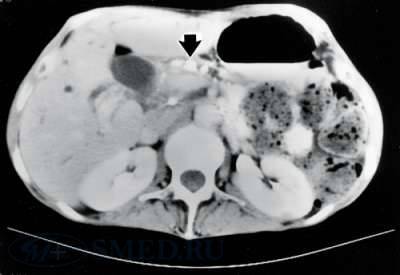

Рис. 3. КТ снимок. Стрелкой указаны кальцификаты в просвете протока поджелудочной железы.